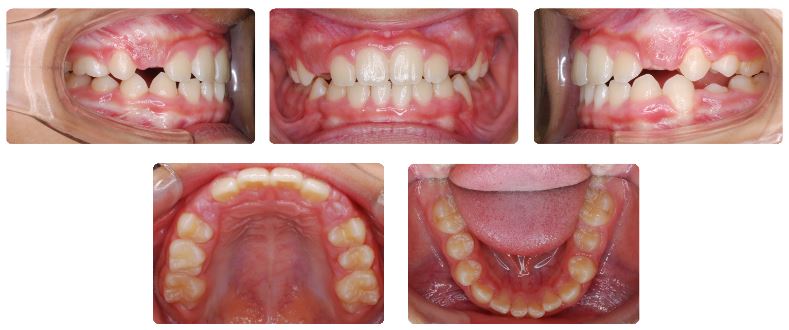

前歯の歯並びに少し隙間ができたタイミングで、マウスピース型の機能的矯正装置であるトレーナーを混合歯列期の間、現在まで使用しています。

初診時から現在まで使用した装置は取り外し式の拡大装置を半年間とトレーナーのみです。

毎日のトレーナー装着による舌を含めた機能トレーニングの成果です。

永久歯列期になる前のこの時期ならではの治療効果です。